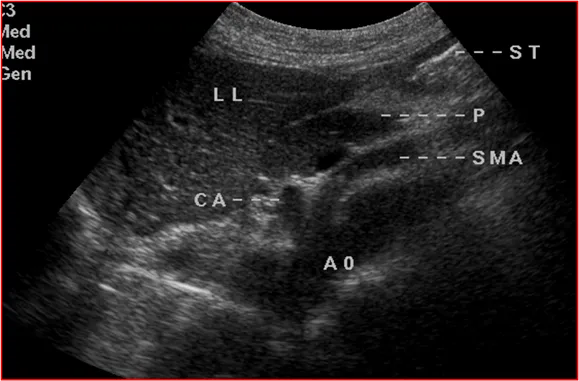

上腹部横切显示胰体部占位与腹腔干的关系

上腹部横切显示胰尾部占位压迫脾静脉呈“Z”形

饮水后上腹部横切,显示胰尾部占位与胃体后壁的关系